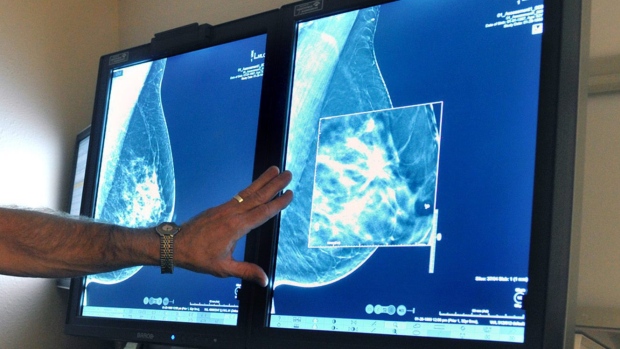

(Eric Gaillard/Reuters)

(AP Photo/Kevin Wolf)

(Christer Waara/CBC)